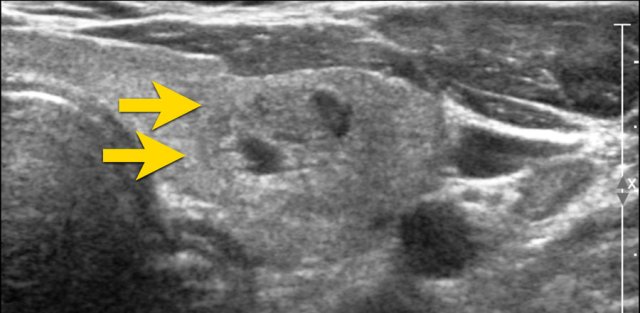

Ill-defined nodule.

Notice how only some small parts of the border of the nodule can be defined (arrow).

Most of its margin is indistinct from the thyroid parenchyma.

0 points in TI-RADS.